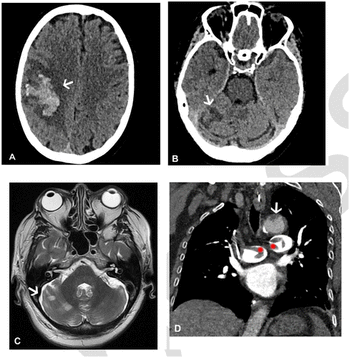

A 3D whole brain convolutional neural network could provide enhanced sensitivity and specificity for diagnosing intracranial hemorrhages on computed tomography, according to new research presented at the Society for Imaging Informatics in Medicine (SIIM) conference in Kissimmee, Fla.